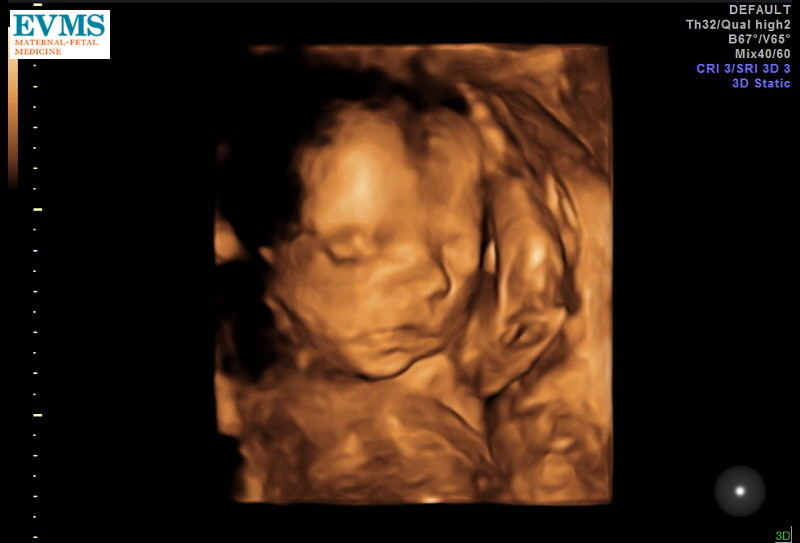

But in the meantime....LOOK AT THAT FACE!!! 😍

Baby girl's cute little face at exactly 28 weeks 😍